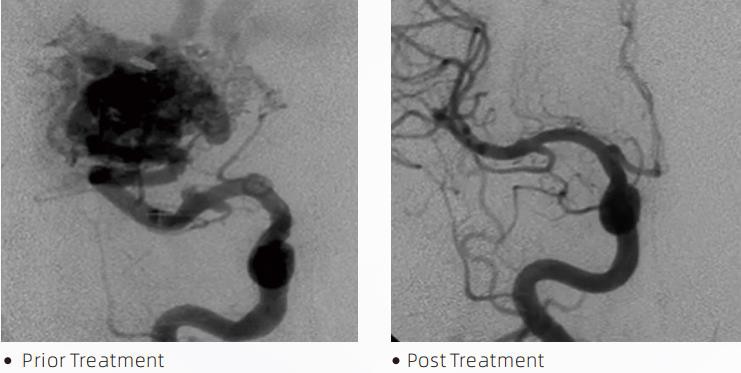

LávaTMLiquid Embolic System je intervenční endovaskulární terapie pro léčbu cerebrovaskulárních malformací. Cerebrovaskulární malformace označuje skupinu benigních nebo maligních neurovaskulárních abnormalit, které mohou vést k intrakraniálnímu krvácení, mozkovému infarktu, cerebrální ischemii a dalším onemocněním. Kapalný embolizační systém je zdravotnický prostředek podávaný jednoduchou intravaskulární inzercí, která embolizuje abnormální mozkové krevní cévy injekcí speciálního tekutého materiálu. Tekutý materiál vytváří řízenou tkáňovou embolii v krevních cévách, což může snížit dopad cerebrovaskulárních malformací na pacienty. Pro přístup k místu embolizace se používá zaváděcí mikrokatétr kompatibilní s DMSO, který je indikován pro použití v neurovaskulatuře. Lávové tekuté embolizační činidlo je neadhezivní systém tekutého embolizačního činidla skládající se z kopolymeru EVOH (ethylenvinylalkohol) rozpuštěného v DMSO (dimethylsulfoxid) a suspendovaného mikronizovaného tantalového prášku pro zajištění kontrastu pro vizualizaci pod fluoroskopií. LávaTMje k dispozici ve třech složeních produktů, LAVA-12, LAVA-18 a LAVA-34. LAVA-12: Doporučeno při krmení distálních mikrocév a prostřednictvím malých podavačů. LAVA-18: Doporučuje se při podávání injekcí pediklu v blízkosti nidu; LAVA-34: Doporučeno pro embolizaci vyššího toku a větších píšťalových komponent.